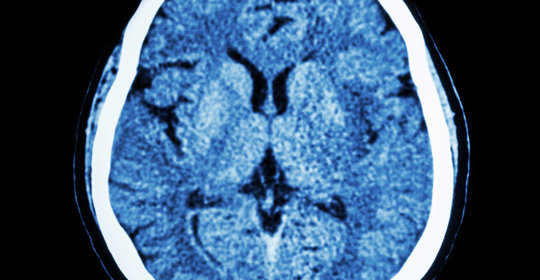

硬腦膜外血腫:破解腦部危機,看懂這些症狀,掌握治療方法

硬腦膜外血腫是常見的顱腦傷害之一,可導致顱內壓升高和神經功能障礙。瞭解硬腦膜外血腫的症狀和治療方法有助於及時診斷和治療,降低併發症和死亡率。本文詳細介紹了硬腦膜外血腫的症狀、診斷、治療和預防方法,旨在提高公眾對這一腦部危急病症的認識。